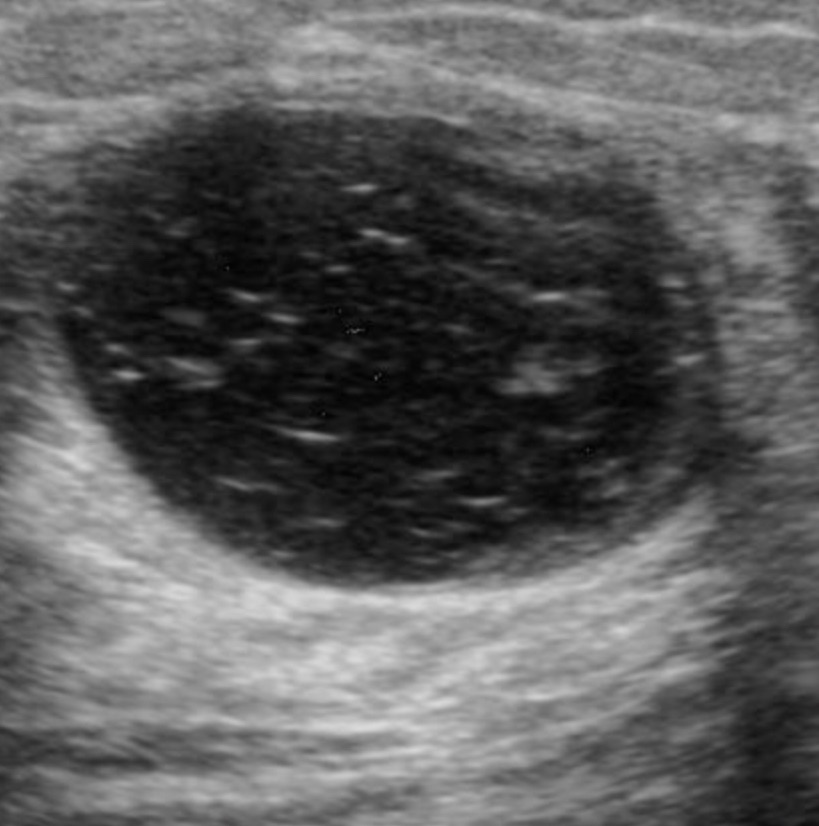

- Complicated cysts (Image):

- Differ from simple cysts:

- Only with regard to internal echoes

- Complicated cysts are circumscribed and show posterior acoustical enhancement:

- But are not anechoic

- They are old cysts that have gradually lost fluid through absorption:

- Leaving behind proteinaceous fluid, cholesterol crystals, blood, or other substances:

- That cause low-level internal echoes

- They can sometimes be difficult to distinguish from hypoechoic solid lesions

- If one can demonstrate swirling of particles within the mass either by “bouncing” the transducer against the lesion or increasing the power of the beam:

- The diagnosis of a cystic lesion can be made

- If there is no movement of particles:

- A solid mass cannot be excluded